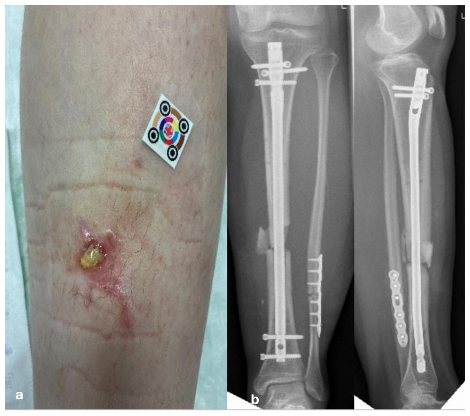

Fistulas, purulent discharge, or persistent wound drainage are sometimes misinterpreted as postoperative irritation. Such misjudgments delay necessary diagnostic and surgical actions, allowing infection progression, jeopardizing implant stability, and risking systemic complications (Metsemakers et al., 2018). International FRI criteria define fistula, pus, or visible purulent drainage as definitive signs of infection (Fig. 1a).

Figure 1(a) A 16-year-old patient with a lower leg fracture classified as Gustillo–Anderson grade III. Initial management involved external fixation, followed by definitive fixation with intramedullary nailing. The patient is currently presenting with a fistula and a fracture-related infection (FRI), often misinterpreted as wound healing disturbance. (b) Anteroposterior and coronal radiographs demonstrating a lower leg fracture stabilized with intramedullary nailing. The images reveal a non-progressive fracture healing pattern with radiological features consistent with fracture-related infection.

Recommended approach

The presence of a fistula or purulent discharge indicates a manifestation of FRI and requires timely surgical intervention, including careful debridement, multiple deep-tissue samples, the restoration of stability, and targeted systemic and/or local antimicrobial therapy. Rapid structured management is crucial to prevent progression, chronic infection, and functional loss.